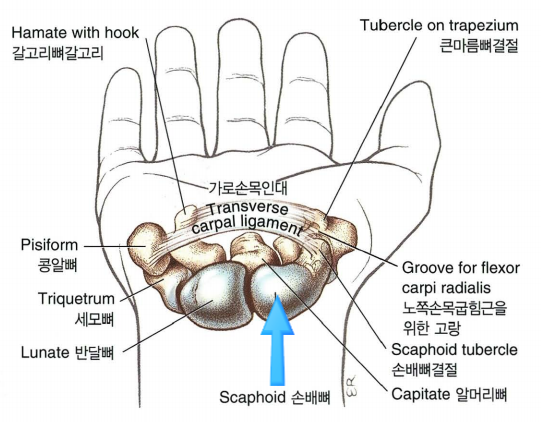

2. 해부학

- 손목에 작은 뼈들은 8개로 구성되어있습니다.

- 근위열 4개뼈

- 주상골(scaphoid), 월상골(Lunate), 삼각골(Triquetrum), 두상골(Pisiform)

- 원위열 4개뼈

- 대능형골(Trapezium), 소능형골(Trapezoid), 유두골(Capitate), 유구골(Hamate)

- 근위열 4개뼈